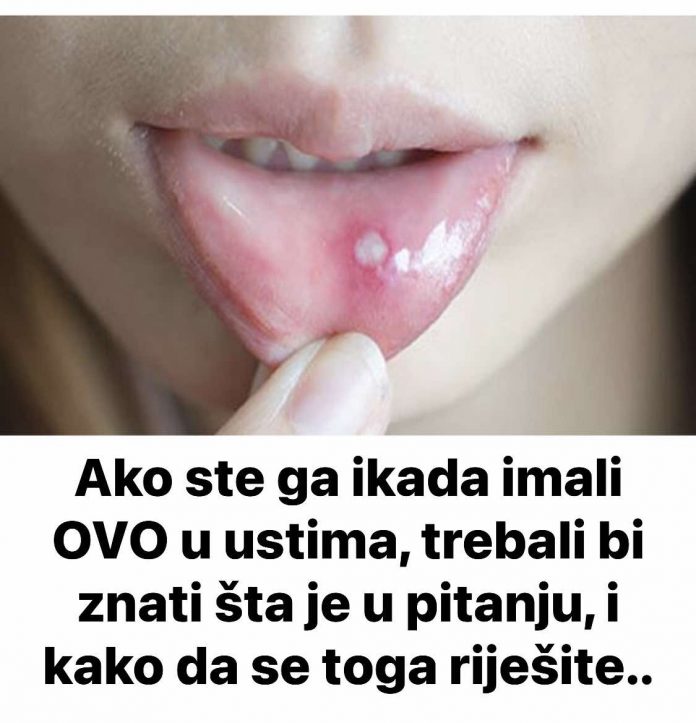

U današnjem članku istražujemo problem afti, malih, bolnih ulceracija koje se često javljaju unutar usne šupljine, a koje mogu značajno utjecati na kvalitet života osobe koja ih ima.

Afte su obično bijele ili žute boje s crvenim rubovima i mogu varirati u veličini. Najčešće se javljaju na unutrašnjoj strani usana, obrazima, jeziku ili u dnu usne šupljine. Mogu trajati od nekoliko dana do dvije sedmice, a nakon toga se obično zacjeljuju bez ostavljanja ožiljaka. Iako nisu ozbiljno zdravstveno stanje, afte mogu značajno smanjiti kvalitetu života. U ovom članku ćemo se fokusirati na uzroke afti, njihove simptome i prirodne tretmane koji mogu pomoći u ublažavanju nelagode.

- Pojava ranica: Afte obično izgledaju kao bijele ili žute ranice s crvenim rubovima unutar usne šupljine. One mogu varirati u veličini, a ponekad ih ima više u isto vreme.